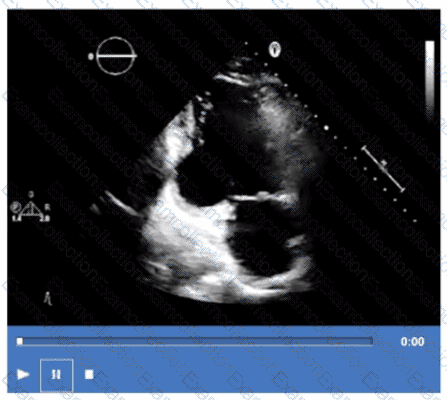

What is the regional wall motion assessment of the two-chamber view displayed in this video?

Which coronary artery territory is associated with the wall motion abnormality demonstrated in this video?